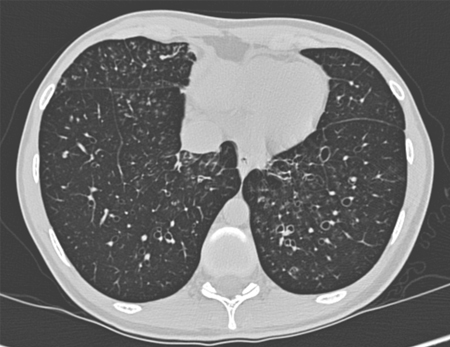

Bronquiectasia

Bronquiectasia cística e varicosa grave em um homem de 49 anos de idade com bronquiectasia idiopática e escoliose

De Pamela J. McShane, MD; uso autorizado